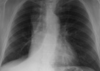

Pneumothorax